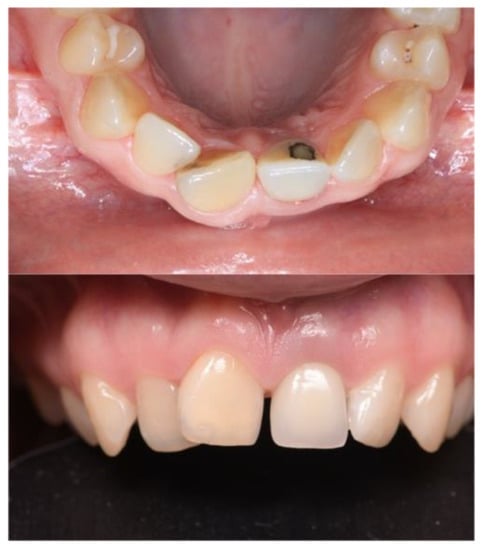

3.1. Case No. 1

3.2. Case No. 2